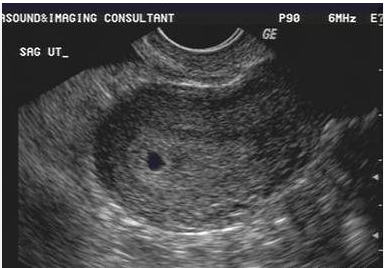

四、验孕成功

后回国等待验孕,就在移植的第9天后,我们收到了钱女士的好消息,HCG185.21,成功怀上了。